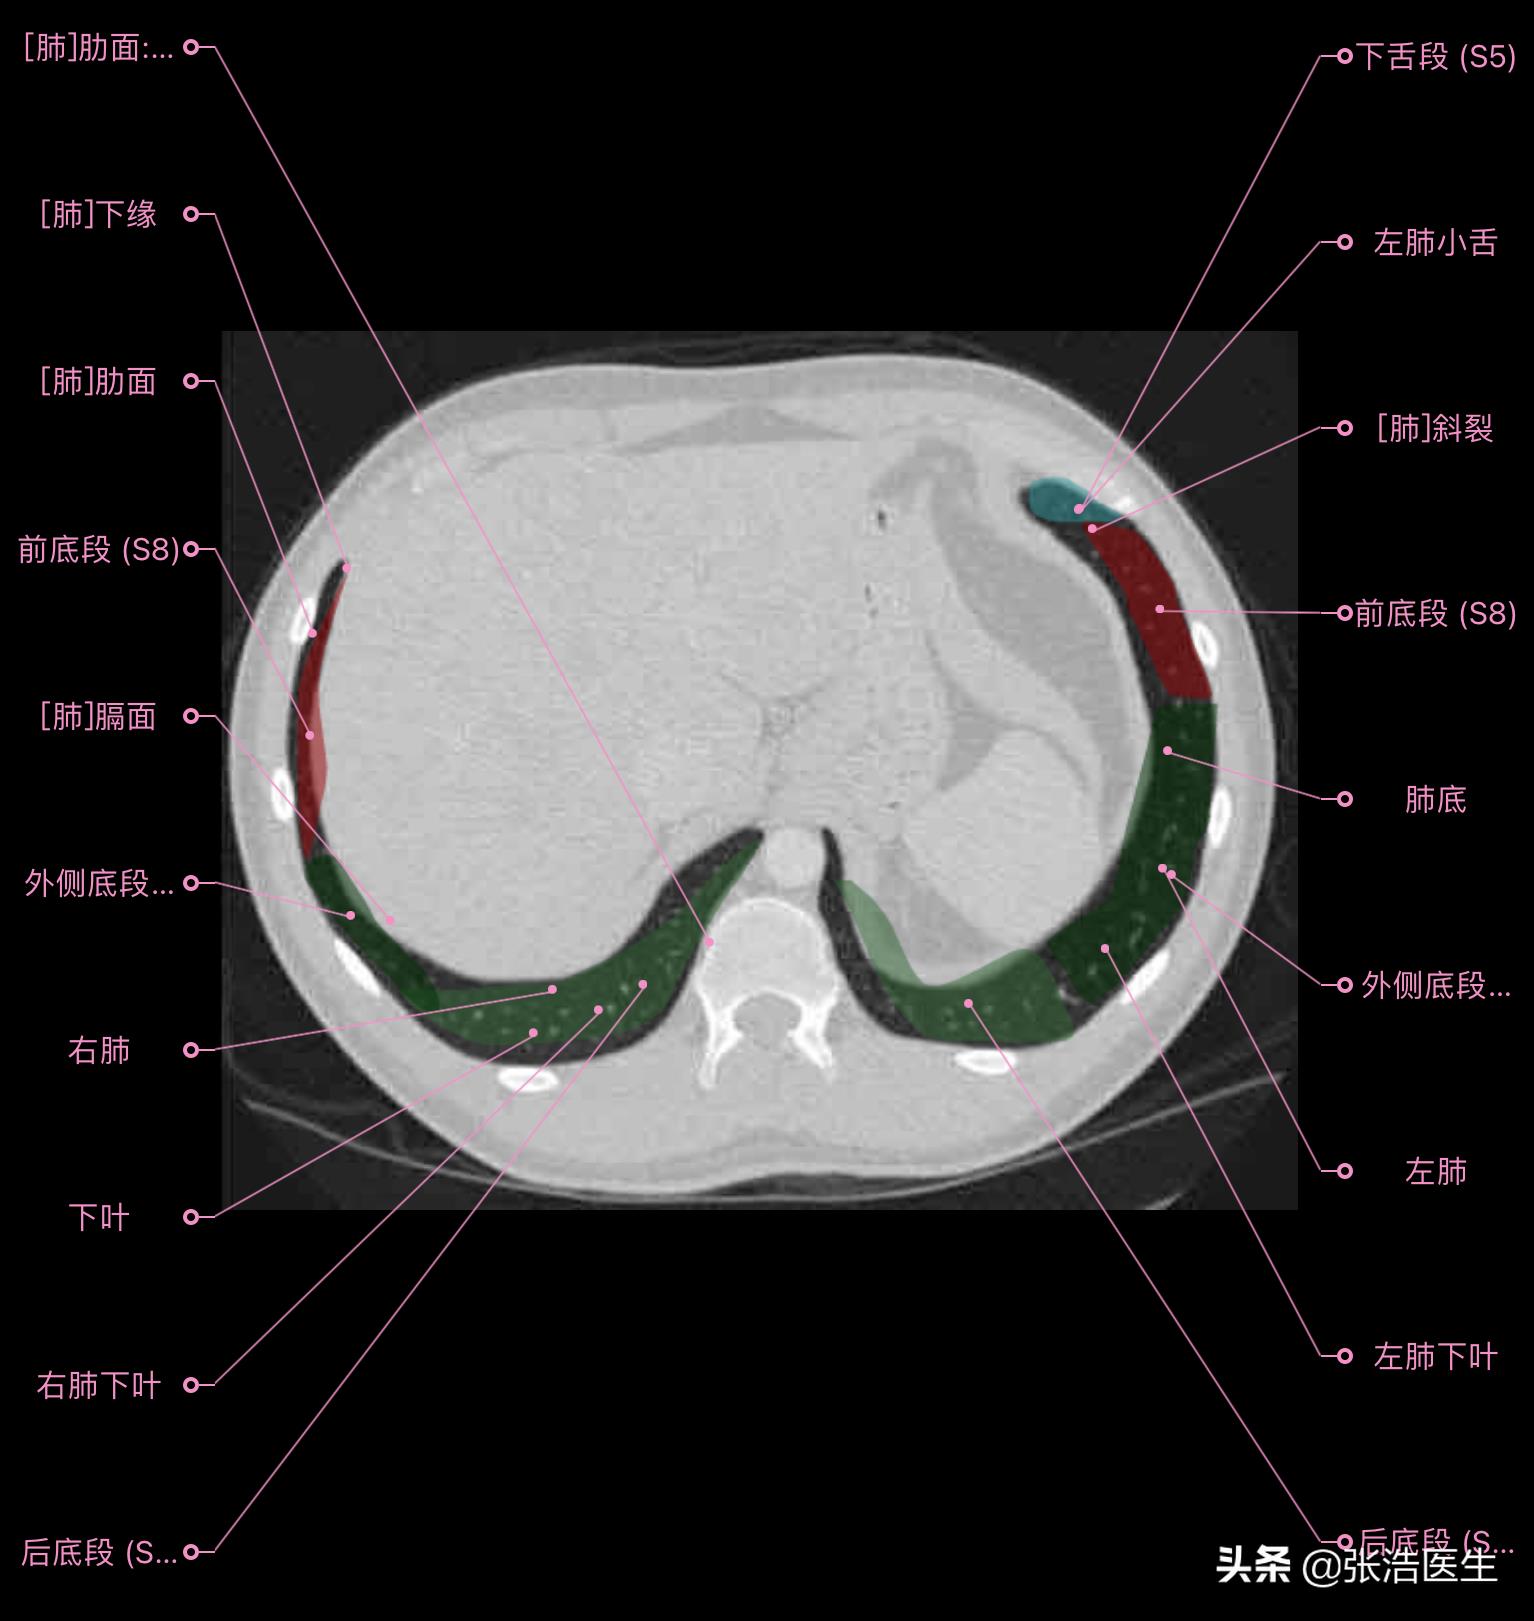

肺部CT横断面 高清解剖图谱

精选15层常用解剖断面

每一层都带有详细标注,值得收藏学习!

肺部CT横断面高清解剖图谱(图层10)